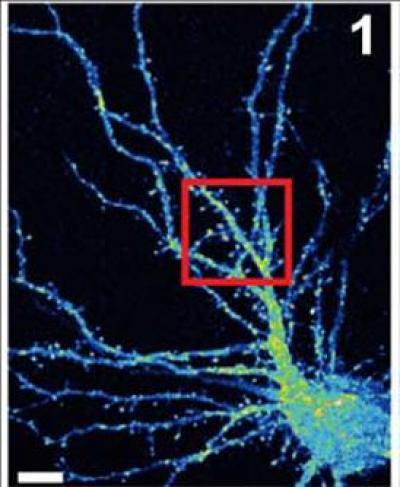

False color image of a mouse hippocampal neuron (cell body is at lower right) with branchlike dendrites that provide surfaces at which projections from other neurons can connect, by forming synapses. Van Aelst and colleagues have shown that when the OPHN1 protein is mutated, interfering with its ability to interact with another protein called Homer1b/c, AMPA receptors don't recycle to the surface at synapses at the rate they normally do. This adversely impacts synaptic plasticity, the process by which neurons adjust the strength of their connections. Such pathology may play a role in X-linked mental retardation. Credit: Van Aelst Laboratory, CSHL